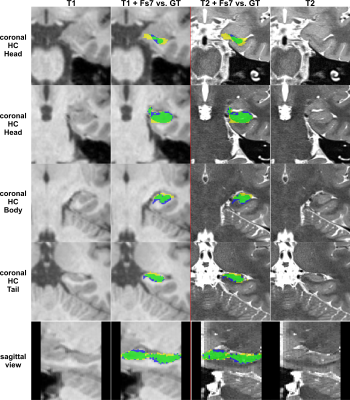

Figure 4: FreeSurfer segmentation. Columns left to right: 1. shows T1 patch; 2. shows comparison of the T1-based FS7-mask vs. the GT; 3. shows the T1+T2 based FS7-mask vs. the GT; 4. shows the registered T2 patch. Top four rows depict coronal slices of the HC-head, HC-body, and HC-tail. The last row shows a sagittal slice with the mask comparison. Legend: green = True Positives, yellow = False Positives, blue = False Negatives; FS7-mask/CNN-mask = yellow+green, manual GT = green+blue.